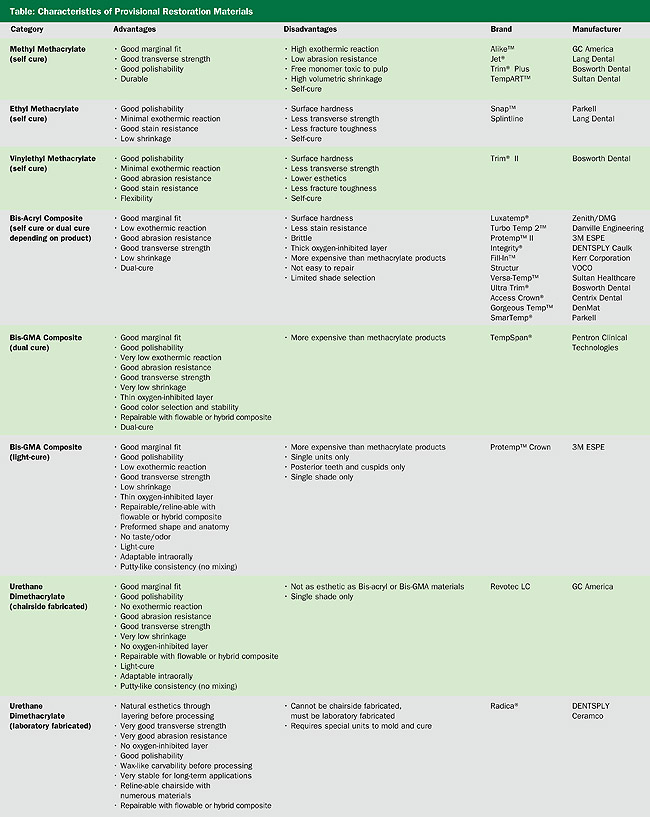

Provisional restoration materials need to fulfill the specific criteria of mechanical, esthetic, and biologic properties.1 With this in mind, the materials available fall into basic types, based on their basic chemistry, with each category having advantages and disadvantages.